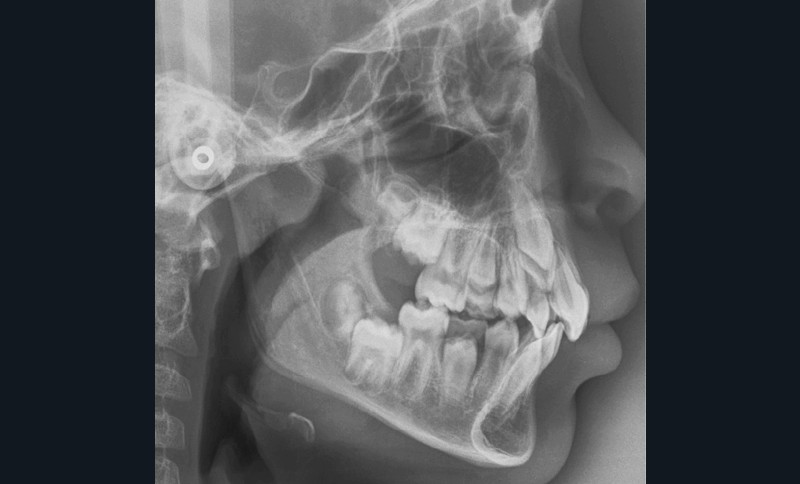

Antony, 11 ans se présente initialement pour une demande esthétique concernant ses deux incisives centrales qu’il trouve trop grosses (fig. 1a-c).

Le profil est convexe et associé à une inocclusion labiale au repos. Il s’agit d’une classe II squelettique sur un schéma facial normodivergent. Les rapports occlusaux sont de classe II bilatérale (complète au niveau molaire) avec des incisives inférieures vestibulo-versées. La 21 est géminée et la 11 vraisemblablement fusionnée avec un germe surnuméraire, sans altération de la formule dentaire. Du fait du diamètre mésiodistal fortement augmenté des incisives centrales, et du manque de place à l’arcade maxillaire qui en découle, les 12 et 22 sont en inversé d’occlusion en palato position. Les 53 et 63 sont persistantes sur l’arcade avec une inclusion en transposition incomplète de la 13, dont la cuspide se situe entre la racine de la 12 et celle de la 11 résorbée (fig. 1d-g).